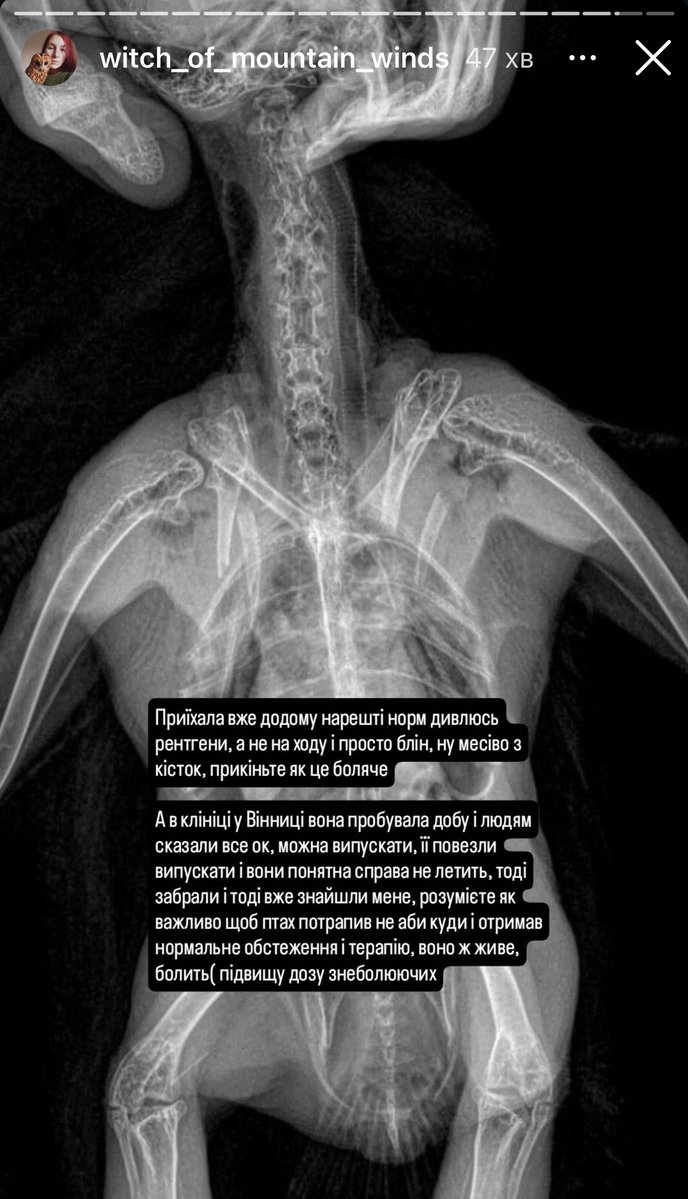

Вет клініка у Вінниці, яка регулярно гробить тварин. Вже писала про них раніше, і от чергова історія. Не знаю наскільки криворуким «спеціалістом» треба бути, щоб не побачити ШІСТЬ МАТЬЙОГОВЙОБ ПЕРЕЛОМІВ 🤬 «Всьо ок, можна випускать в природу» 🤡